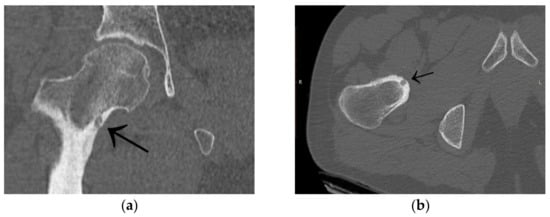

3.1. Case 1: OO Masking as Femoroacetabular Impingement (FAI)